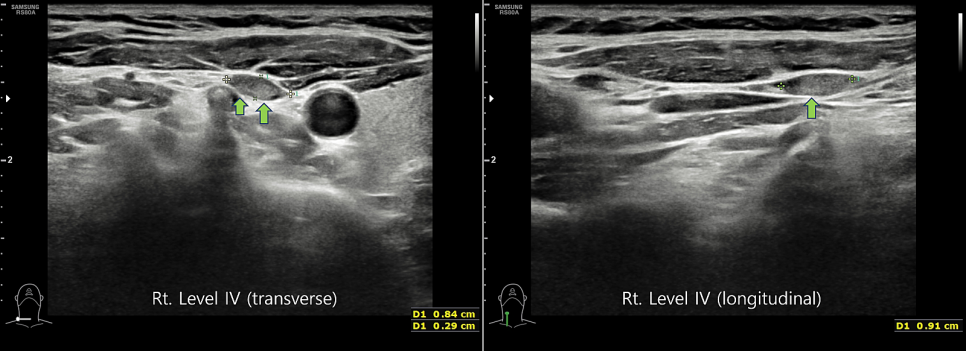

림프절 전이를 알아보기 위해 경부 림프절 초음파 검사를 통해 관찰해 보았습니다.

오른쪽 4구역 림프절로 녹색 화살표 부분에 회색 덩어리가 약간 보입니다.갑상선암 전이의 소견입니다.